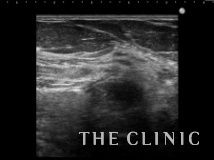

吸引した壊死脂肪です。

ほとんどしこりは無くなり、触診でも触れなくなりました。